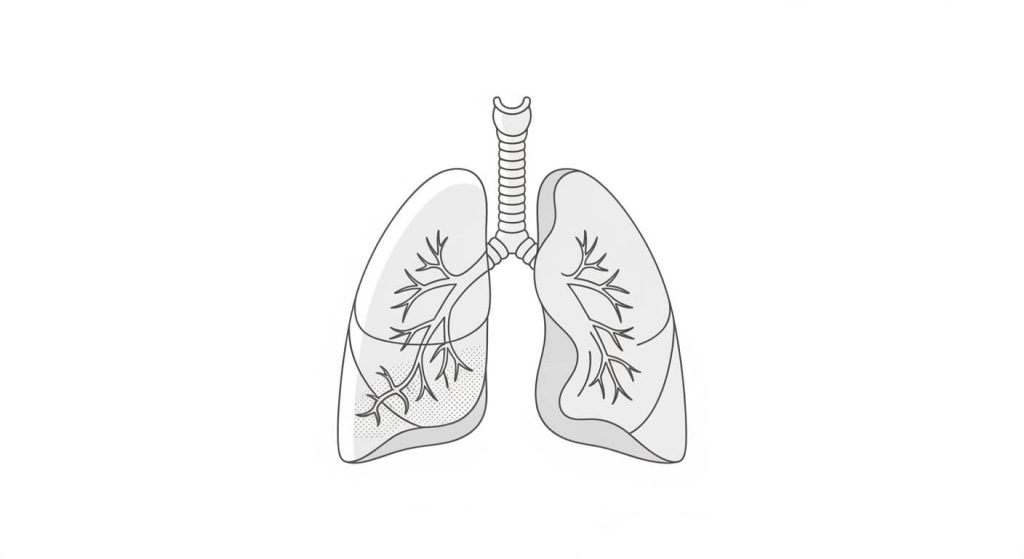

Idiopathic pulmonary fibrosis (IPF) is a long-term lung condition where the tissue in and around the air sacs becomes scarred (fibrosis) over time. As scarring builds up, lungs become stiffer and it becomes harder for oxygen to move into the bloodstream.

Pulmonary fibrosis means lung scarring. Idiopathic pulmonary fibrosis is the term used when scarring develops and no clear cause is found after medical evaluation.

Why scarring matters

Scar tissue does not function like healthy lung tissue. Over time, the lungs may lose elasticity, breathing can feel more difficult, and everyday activities can become more exhausting.